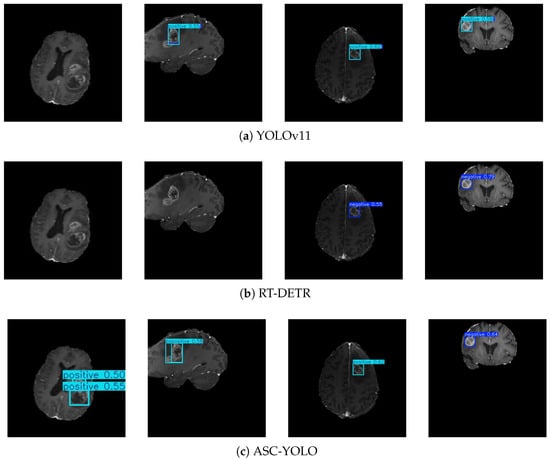

3.3. Generalization Analysis

3.3.1. Dataset Preparation

3.3.2. Results of the Experiment

| Models | Parameters | Recall | mAP@50 | mAP@50-95 |

|---|---|---|---|---|

| YOLOv11 | 5.1 | 0.520 | 0.532 | 0.343 |

| RT-DETR | 8.3 | 0.490 | 0.501 | 0.309 |

| ASC-YOLO | 2.9 | 0.550 | 0.602 | 0.412 |